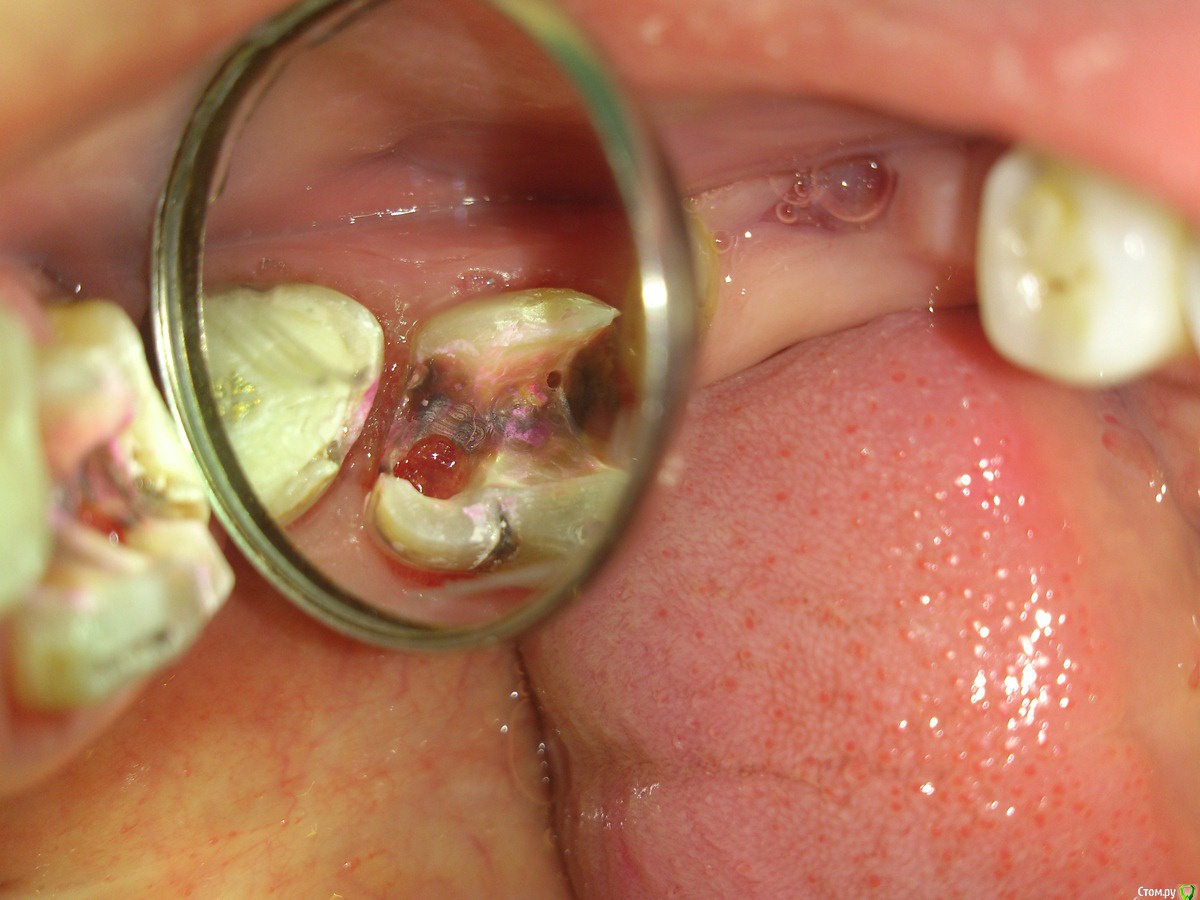

Shamxal Опубликовано 4 декабря, 2014 Поделиться Опубликовано 4 декабря, 2014 Есть ли смысл закрывать перфорацию на 26 зубе в области трифуркации размером в головку зонда? Пациент в таком состоянии поступил в клинику в 3 часа ночи под рукой не было хорошего фотика. У зуба есть шанс? Ссылка на комментарий

sydnik Опубликовано 4 декабря, 2014 Поделиться Опубликовано 4 декабря, 2014 а где тут зуб? Ссылка на комментарий

Dr.Kleiner Опубликовано 9 декабря, 2014 Поделиться Опубликовано 9 декабря, 2014 Только удалять, от него вообще ничего не осталось. Ссылка на комментарий